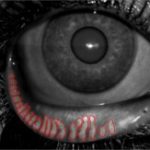

DryAI

Quantification automatique et reproductible des symptomes de la sécheresse oculaire